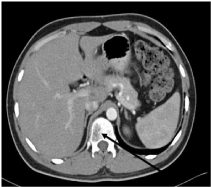

The patient complained of low back ache in the workup period for which a dorso-lumbar spine X-Ray was obtained which was normal. A Contrast enhanced computed tomography (CECT) chest and abdomen was advised keeping a high index of suspicion in view of a high grade DLBCL. The CECT revealed multiple ill defined lytic lesions noted in the bodies of C7, DV4-DV6, DV10, DV12, LV2, SV1 and bilateral iliac bones. Also, a compression fracture of DV4 was noted. Rest of the metastatic workup including the bone marrow study was normal. With the clinical stage IV disease, patient was started on RCHOP chemotherapy regimen. As part of the RCHOP regimen the patient received eight cycles of Inj Rituximab (375mg/m2), Inj Cyclophosphamide (750mg/m2), Inj Doxorubicin (50mg/m2), Inj Vincristine (1.4mg/m2) and Tab Prednisolone 40mg/m2/day for 5days. The chemotherapy was well tolerated. Presently, the patient is disease free after one year and is on regular follow up (Figures 9 & 10).

Figure 10 CECT abdomen revealing the lytic area in the body of the vertebra (arrow).